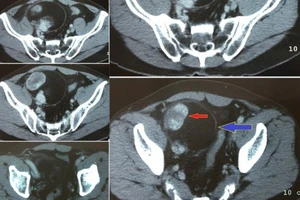

Bệnh nhân chảy máu ồ ạt ngay trên bàn mổ